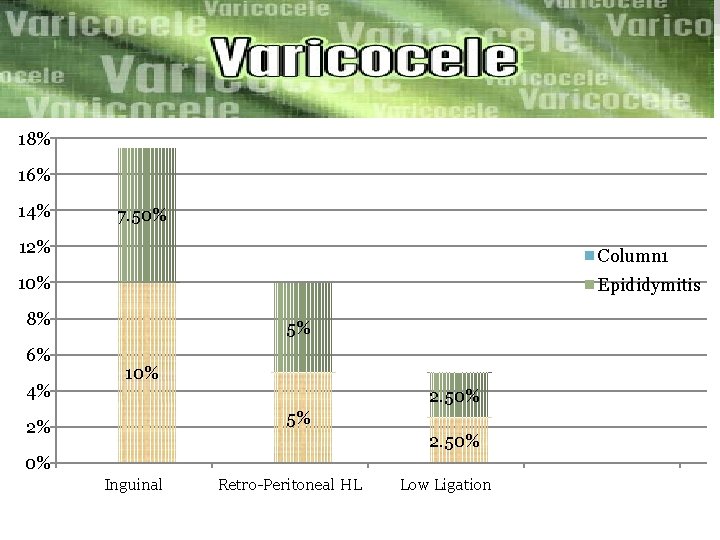

ØWe compare the outcomes of three microsurgical techniques: inguinal high ligation (IHL) =40 patient Retroperitoneal high ligation(RHL) =40 patient Low ligation(LL) =40 Patient we compared the operation time, post operative complication Recurrence rate. The result was…………….

18% 16% 14% 7. 50% 12% Column 1 10% Epididymitis 8% 6% 4% 5% 10% 2. 50% 5% 2% 2. 50% 0% Inguinal Retro-Peritoneal HL Low Ligation